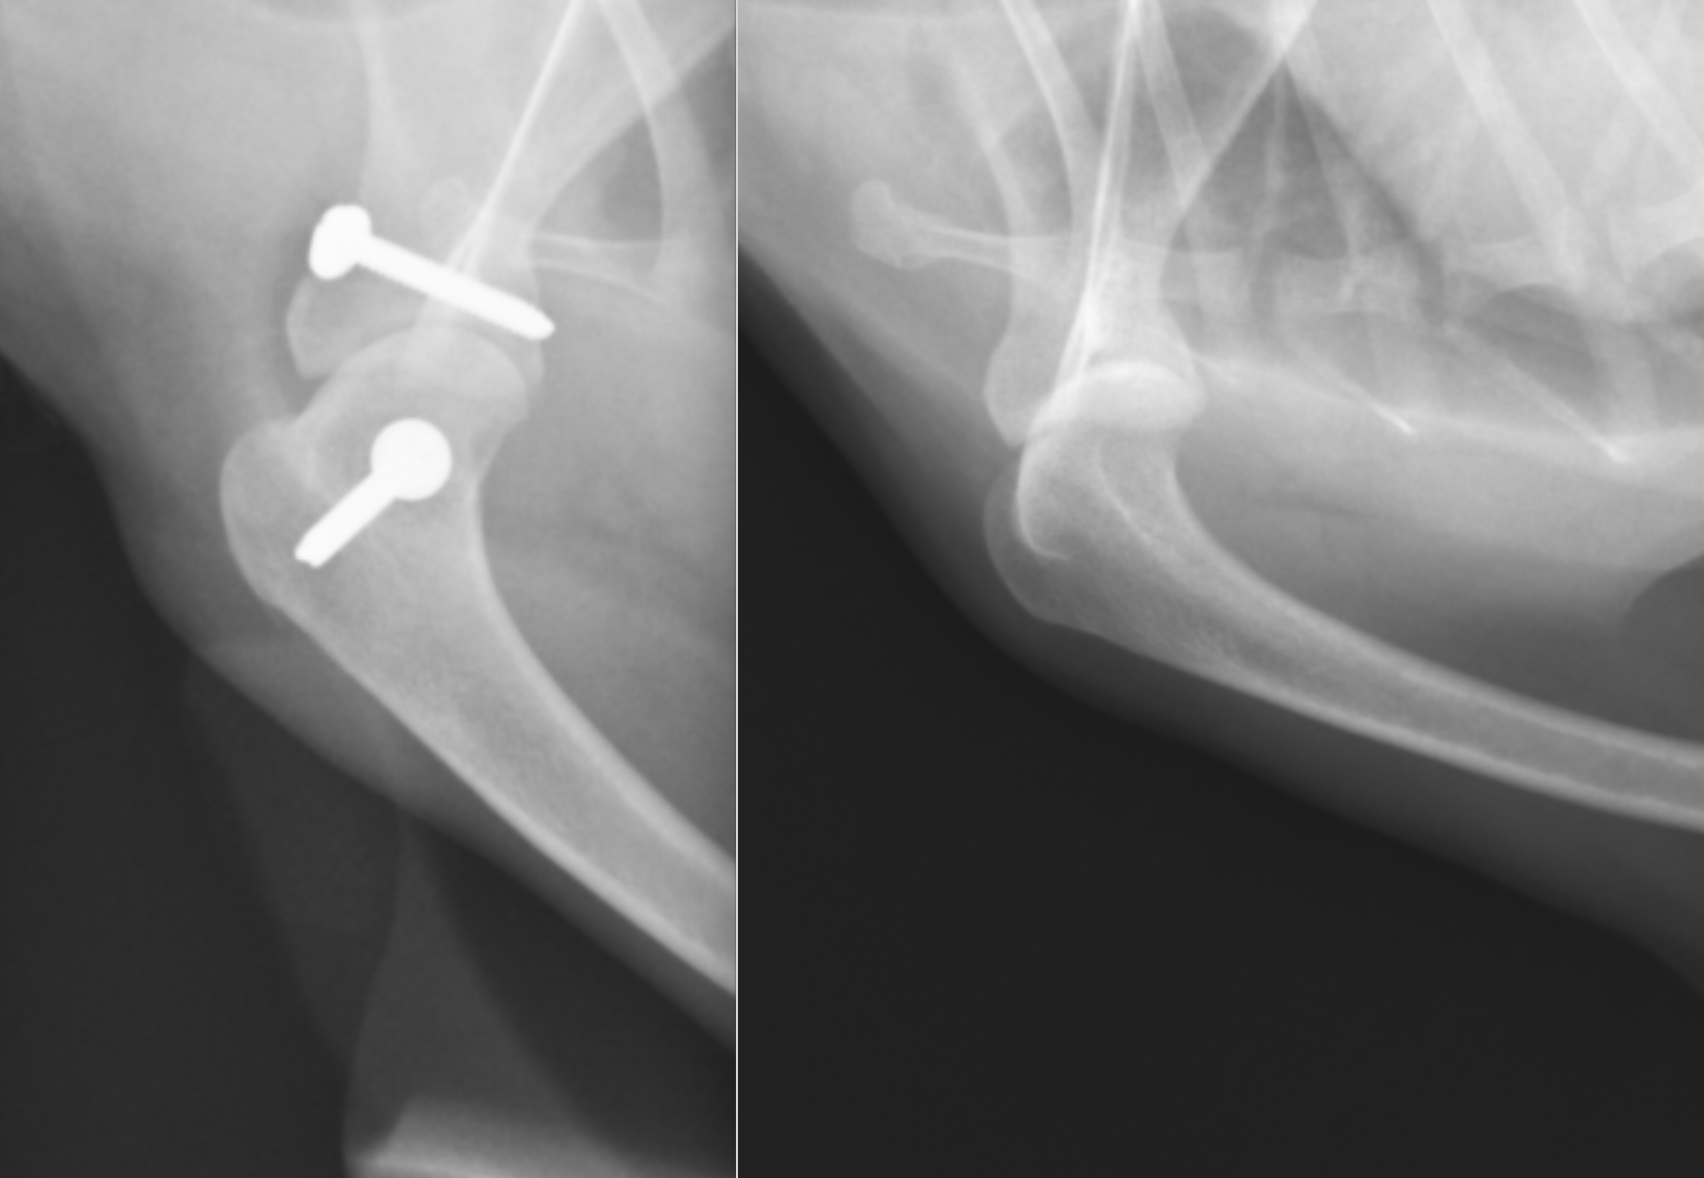

右肩関節脱臼のX線画像です。向かって左の青い矢印がずれているのがわかります。下の上腕骨が内側に入ってしまっているのです。正常な反対は緑矢印が合っているのがわかります。

術後のX線画像です。ワッシャーとスクリューが入っているのが確認できます。また、ずれていた矢印の骨がぴったりと合い、関節がはまっているのがわかります。